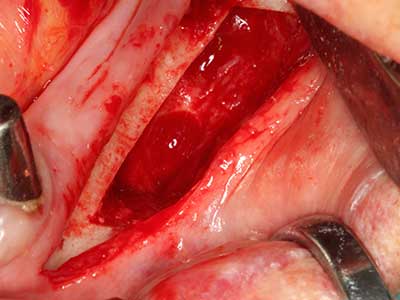

Piezo surgery has additional advantages when harvesting bone blocks. In addition to the high precision with osteotomy described above, the use of the thin saw tips specifically minimizes loss of material. Greater loss of material during harvesting can be expected with the thicker instrument tips, particularly when using Lindemann drills (Lakshmiganthan, Gokulanathan et al. 2012). The basal separation, which is necessary particularly for retromolar block transplants, is simplified by specially designed rectangular saws, with the result that piezo surgery is viewed as a precise, simple and safe procedure for harvesting retromolar bone blocks (Happe 2007) (Fig. 1-12).